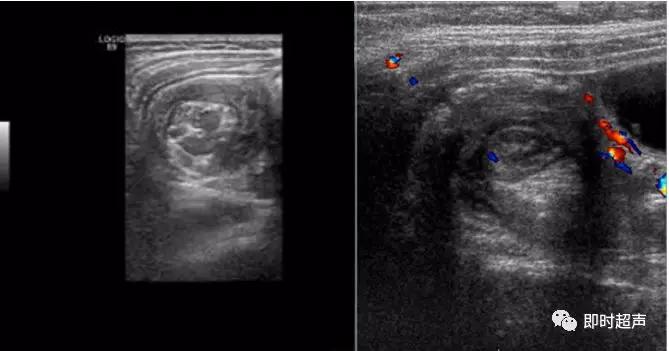

短轴位显示为靶环征,阑尾壁血流信号增多;长轴位显示阑尾增粗,压之不变形,管壁不均匀增厚,最大直径超过6mm。

间接征象:阑尾周围脓肿,表现为形态不规则、边界模糊的混合回声或低回声团块;盆腔/腹腔积液;阑尾周围肠系膜脂肪组织、大网膜炎性改变,表现为条带状、絮状、片状高回声围绕包裹;阑尾腔内粪石伴声影;粘连性肠梗阻、腹膜炎,肠腔减缓蠕动、相邻肠管积液积气、扩张。

阑尾炎超声声像图

腊肠征与同心圆征

包块与粪石